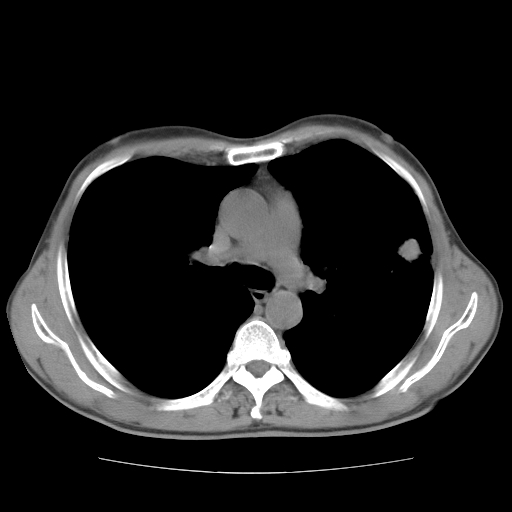

以下是引用随光逐影在2008-11-20 23:02:00的发言:[br]1)考虑左肺上叶周围型肺癌可能性大。2)两肺散在性肺泡积血。[br][br][本贴已被 随光逐影 于 2008-11-20 23:09:31 修改过]

以下是引用drzhang8888在2008-11-20 22:20:00的发言:[br]密集的短毛刺,血管集束,胸膜凹陷,周边型肺癌可能性大,另双肺多发磨玻璃影,考虑感染

以下是引用流浪星在2008-11-20 22:28:00的发言:[br]左肺上叶近外围区见一类圆形结节影,毛刺征、胸膜尾征阳性,临近肺组织见多发渗出灶。考虑1,炎症性病变。 2.周围性肺癌。建议抗炎治疗后复查。

以下是引用qc80012345在2008-11-21 5:53:00的发言:[br]支持;周围型肺癌诊断。增强扫描。